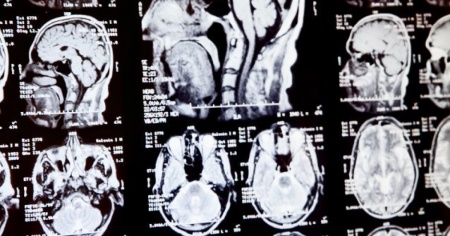

FREDERICTON - Perdita di memoria, atrofia muscolare e allucinazioni. Questi sono alcuni dei sintomi riscontrati in un numero crescente di adolescenti e giovani adulti nella provincia del New Brunswick, in Canada. Gli esperti sono sconcertati, potrebbe essere una malattia neurologica sconosciuta.

Da circa due anni i medici del Canada si stanno ponendo un grosso interrogativo. Sempre più giovani stanno accusando sintomi comuni di quella che potrebbe essere una nuova malattia che colpisce a livello neurologico. Perdono inspiegabilmente peso, hanno spasmi, problemi di equilibrio e la visione che si offusca. I pazienti identificati nella provincia del New Brunswick sono 48, ma potrebbero essere il triplo. Questo perché ci sono numerosi pazienti che aspettano ancora la propria valutazione clinica.

Ciò che si sa di questi pazienti è che prima di presentare i sintomi, non avevano alcuna malattia pregressa, né una predisposizione genetica. Ma il dibattito infiamma, tant'è che molti esperti e la stessa provincia del New Brunswick mettono in dubbio le diagnosi e credono che in realtà le persone toccate non abbiano un morbo misterioso, ma una malattia o una serie di malattie note. Sul sito adibito, la provincia scrive che «i segni e sintomi clinici sono simili a quelli associati alla malattia di Creutzfeldt-Jakob, ma hanno caratteristiche atipiche. A oggi, tutti i risultati dei test sono stati negativi per forme note di malattia da prioni umana».